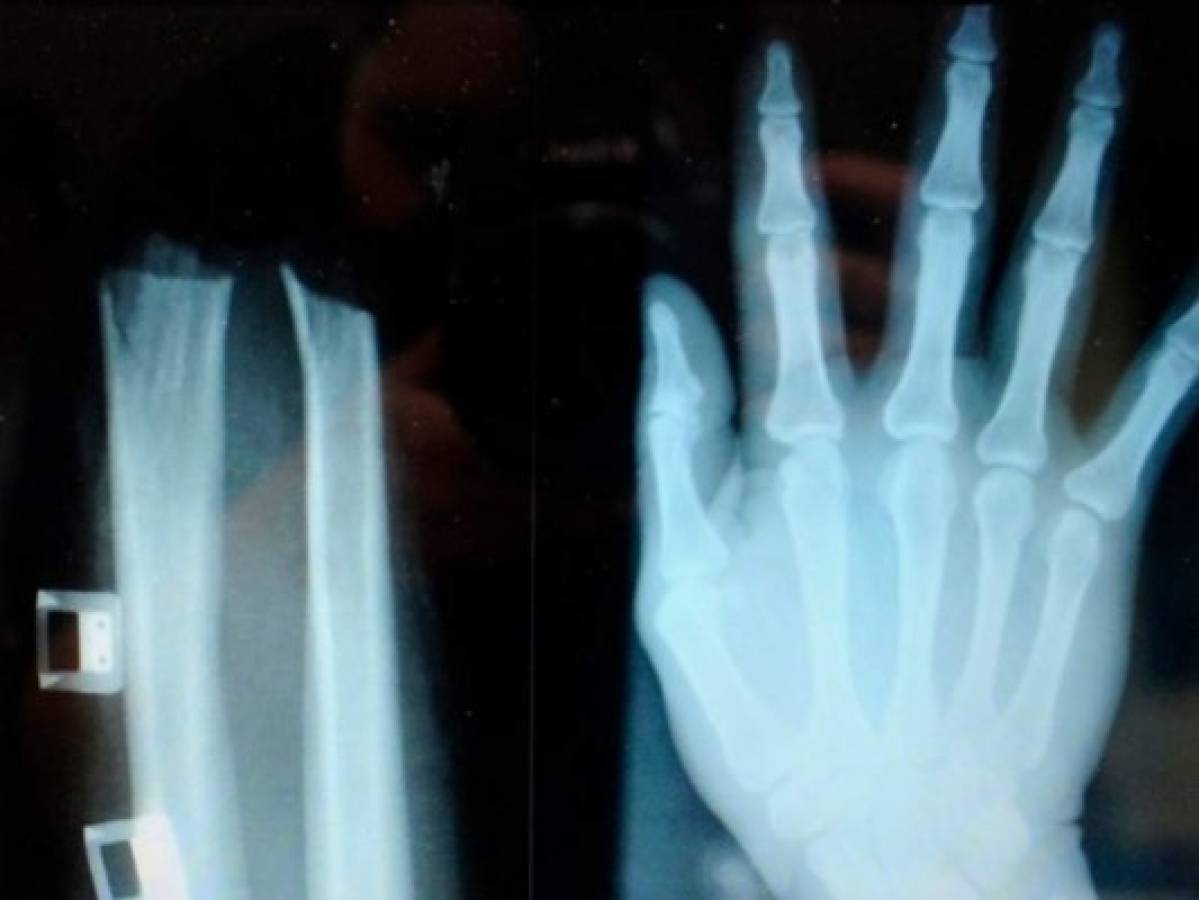

'Junto a un cómplice, se amputó deliberadamente la mano a nivel de la muñeca con una sierra circular con la esperanza de hacer creer que era un accidente', dijo un portavoz de la policía de Liubliana, Valter Zrinski.

La mano pudo ser recosida de urgencia en el hospital universitario de la ciudad.